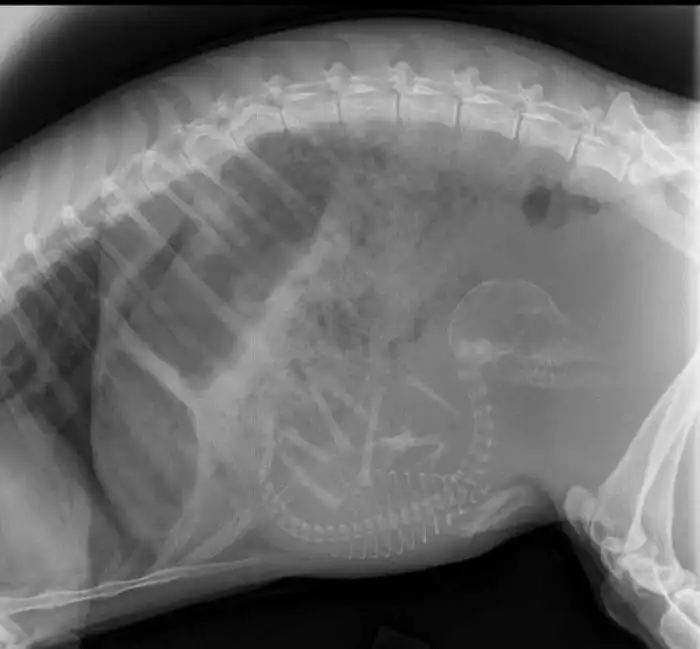

1. Беременная собака